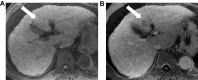

Hepatocellular carcinoma (HCC) is one of the most common tumors worldwide, usually occurring on a background of liver cirrhosis. HCC is a highly vascular tumor in which angiogenesis plays a major role in tumor growth and spread. Tumor-induced angiogenesis is usually related to a complex interplay between multiple factors and pathways, with vascular endothelial growth factor being a major player in angiogenesis. In the past decade, understanding of tumor-induced angiogenesis has led to the emergence of novel anti-angiogenic therapies, which act by reducing neo-angiogenesis, and improving patient survival. Currently, Sorafenib and Lenvatinib are being used as the first-line treatment for advanced unresectable HCC. However, a disadvantage of these agents is the presence of numerous side effects. A major challenge in the management of HCC patients being treated with anti-angiogenic therapy is effective monitoring of treatment response, which decides whether to continue treatment or to seek second-line treatment. Several criteria can be used to assess response to treatment, such as quantitative perfusion on cross-sectional imaging and novel/emerging MRI techniques, including a host of known and emerging biomarkers and radiogenomics. This review addresses the pathophysiology of angiogenesis in HCC, accurate imaging assessment of angiogenesis, monitoring effects of anti-angiogenic therapy to guide future treatment and assessing prognosis.